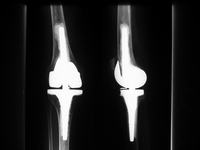

Gekoppelte oder achsgeführte Knieprothese

Bei schweren Abweichungen der Beinachse oder instabilen Seitenbändern ist die Versorgung mit einer der o.g. Prothesen nicht möglich. In diesen Fällen muss eine achsgeführte Prothese eingesetzt werden, bei der die Prothese die Funktion der Bänder übernimmt. Auch dieser Prothesentyp besteht aus einem Ober- und Unterschenkelanteil mit dem Unterschied, dass beide Teile über einen Zapfen oder eine Achse, ähnlich einem Scharnier, verbunden sind.

Durch die Koppelung der Prothesenteile wirken größere Hebelkräfte auf den Knochen und die Prothese, so dass eine größere Verankerungsstrecke im Knochen erforderlich ist, weshalb die Implantate über längere Stiele im Knochen verankert werden müssen.